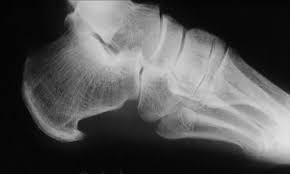

Un espolón es una formación de pico óseo en la zona del talón. Esto se forma por una calcificación en la inserción de la fascia e inflama tejidos colindantes. Produce dolor al levantarnos o tras un período de reposo, tras un tiempo desaparece. El tratamiento se iniciaria con Antiinflamatorios no esteroideos (AINES) y vendajes. Pero el tratamiento final seria soportes plantares. También existe el quirúrgico.